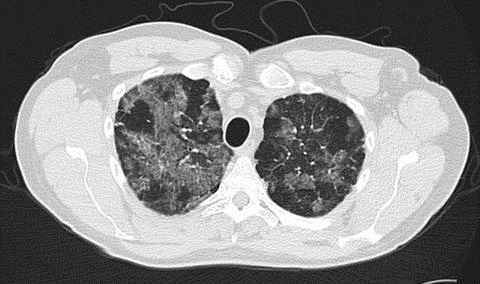

1. Chest X-ray or CT Scan?

- Shows “crazy paving” pattern, indicating lung abnormalities.